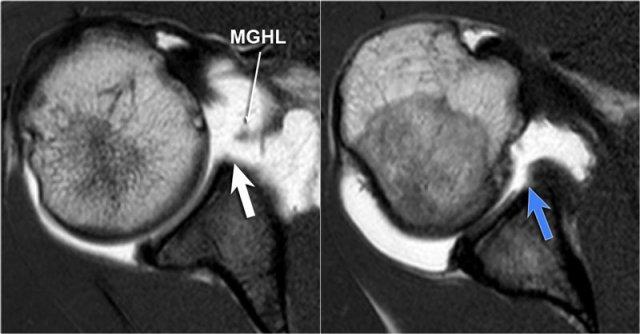

Tổn thương Perthes

Tổn thương Perthes là avulsion sụn viền-dây chằng tương tự Bankart, nhưng với màng xương bị bóc tách về phía trong mà vẫn còn nguyên vẹn.

Trên hình ảnh khớp vai ở tư thế trung gian, sụn viền bị rách có thể được giữ ở vị trí giải phẫu bình thường bởi màng xương bả vai còn nguyên vẹn, từ đó ngăn thuốc tương phản từ thấm vào đường rách.

Điều này có nghĩa là MRI khớp cản từ ở tư thế trung gian có thể không phát hiện được đường rách sụn viền.

Tuy nhiên, ở tư thế ABER, dây chằng ổ chảo-cánh tay dưới bó trước bị căng tạo lực kéo lên sụn viền trước-dưới, giúp tăng khả năng phát hiện đường rách.

Mũi tên chỉ vào màng xương còn nguyên vẹn.

Các hình ảnh ở tư thế ABER cho thấy sụn viền trước bị bong tách.

Hình bên phải được xoay 90° ngược chiều kim đồng hồ.

Đôi khi điều này giúp hiểu rõ hơn về giải phẫu.

Hình ảnh MRI khớp cản từ.

Hình bên trái cho thấy vắng mặt sụn viền trước-trên, được gọi là phức hợp Buford.

Hình bên phải cho thấy khuyết sụn khớp ở vị trí 4 giờ.

Chưa rõ sụn viền có bình thường hay không.

Tiếp tục xem các hình ảnh ở tư thế ABER.